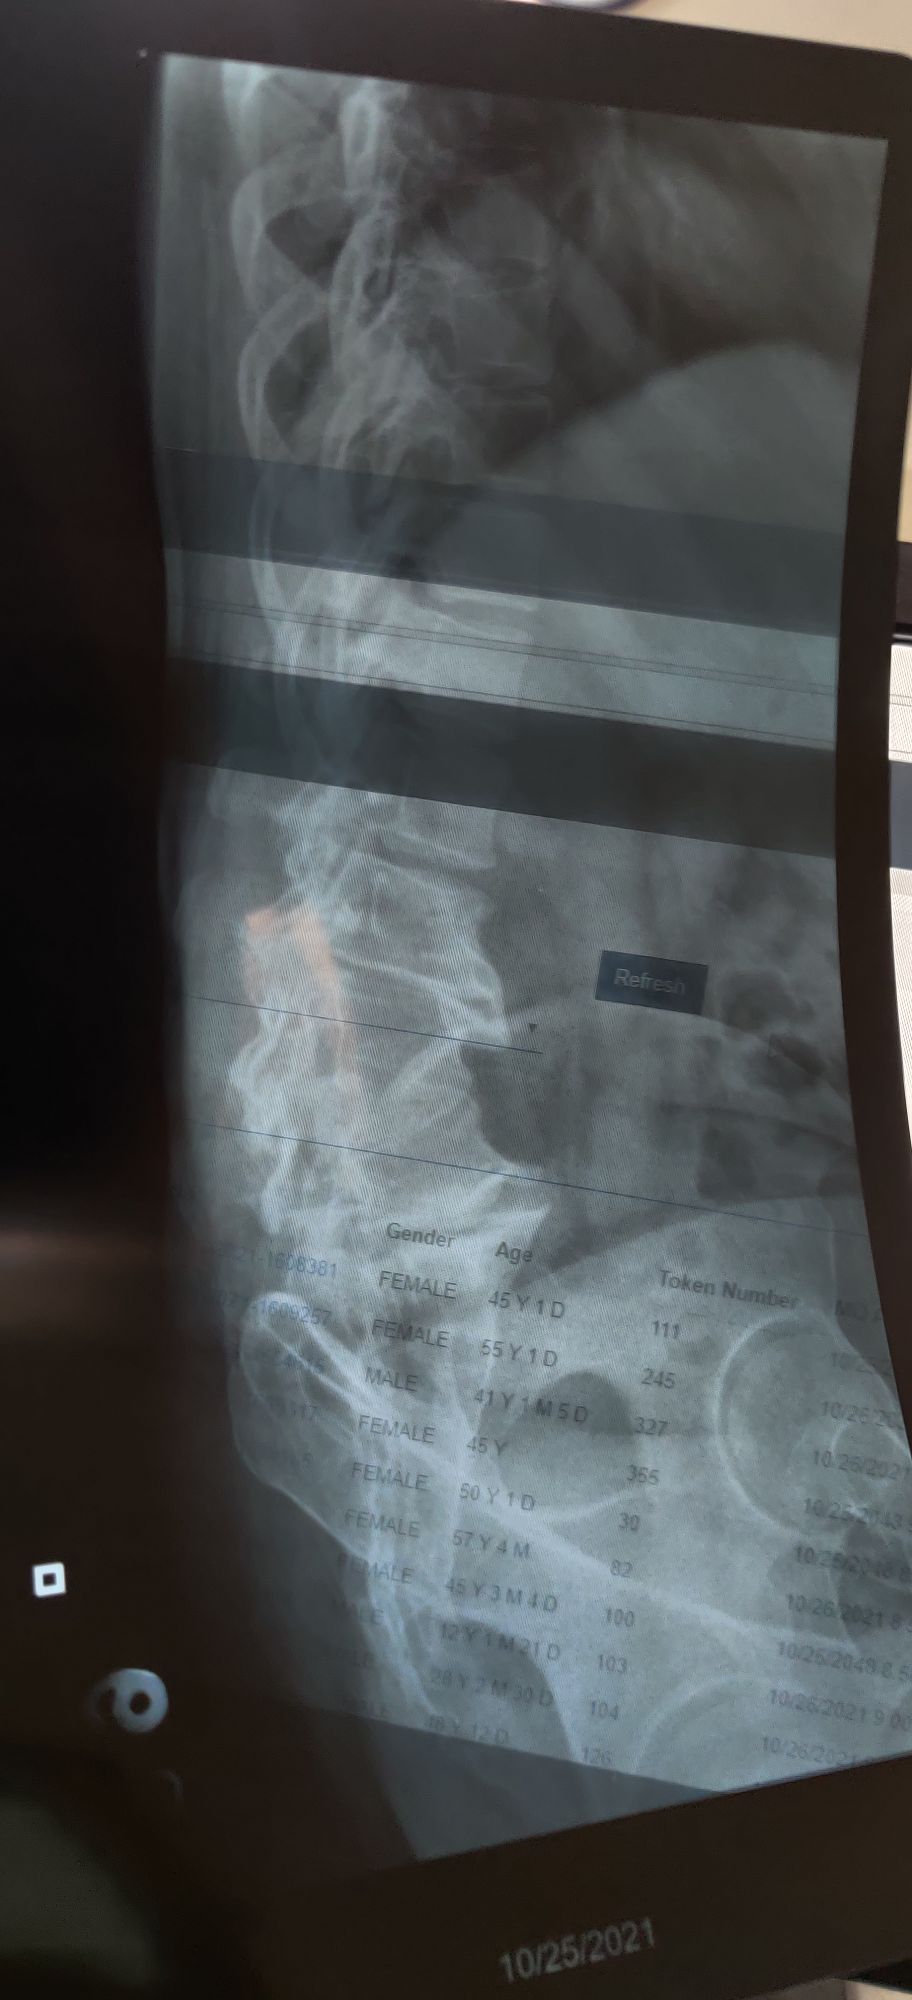

Osteoporosis and OA

Xray

Spine

Ortho